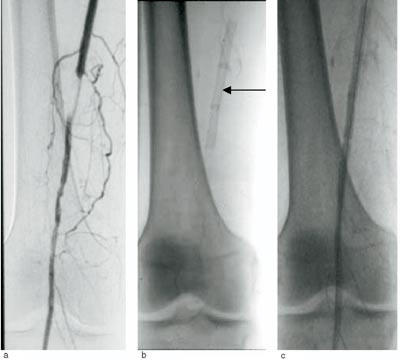

I tidsrommet 1995 – 2001 ble 203 pasienter ved Haukeland Universitetssykehus behandlet med intraluminal angioplastikk for femoropopliteal aterosklerose ovenfor kneet, i alt 264 prosedyrer. 15 tilleggsprosedyrer med stentimplantasjon ble utført (fig 1) hos 12 menn og tre kvinner (median alder 68 år, spredning 56 – 82 år). 14 pasienter hadde i utgangspunktet claudicatio intermittens, mens en hadde kritisk iskemi.

Sju hadde opprinnelig høygradig stenose, mens åtte hadde korte okklusjoner (< 3 cm). Hos 13 pasienter var lesjonen lokalisert i a. femoralis superficialis i adduktorkanalen. En pasient hadde lesjon proksimalt i a. femoralis superficialis, og en hadde lesjon i proksimale a. poplitea. Etter angioplastikk forelå det manglende ekspansjon av lumen hos sju av pasientene, og åtte hadde fått disseksjon som komplikasjon til prosedyren.

Behandling med Wall- og Palmaz-stent i femoralis superficialis og proksimale poplitea er vist å gi omtrent samme resultater (1). Kostnadene ved stentimplantasjon utgjør 4 000 – 8 000 kroner per stent. Av og til kan det være nødvendig å implantere flere stenter for å oppnå ønsket resultat (fig 1b).